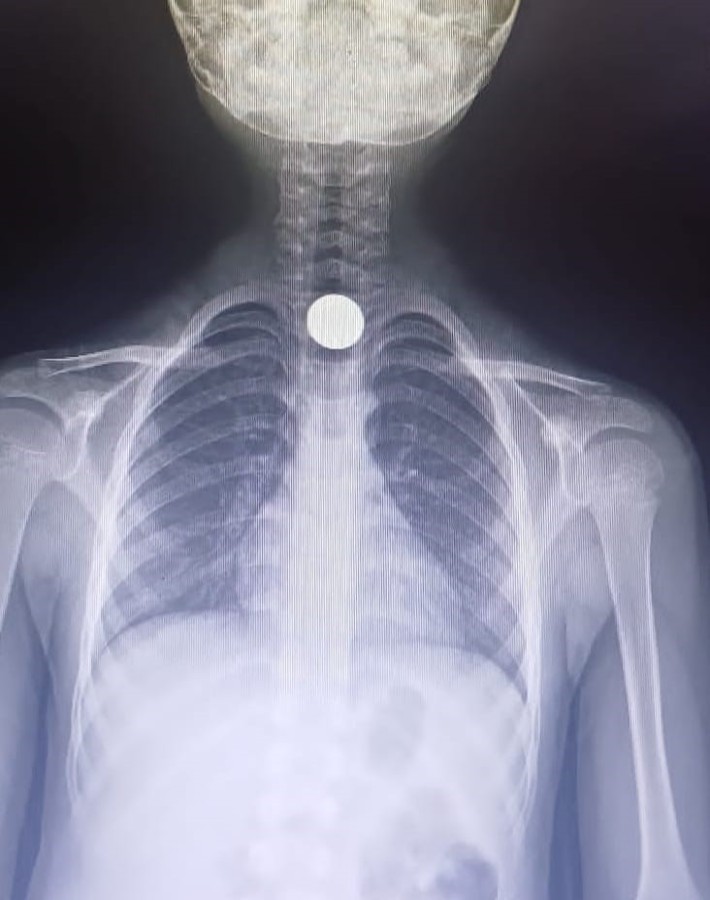

Olay, Baykoca Mahallesi Mimar Sokak'taki apartmanda meydana geldi. 7 yaşındaki Ahmet Eymen U., yerde bulduğu 50 kuruşluk madeni parayı ağzına atıp yuttu. Olayı gören ailesi çocuğu özel araçla İnegöl Devlet Hastanesine götürdü.

Acilde yapılan tetkiklerde paranın yemek borusunda kaldığı tespit edildi. Çocuk, boğazındaki paranın çıkarılması için Bursa Yüksek İhtisas Eğitim ve Araştırma hastanesine sevk edildi.